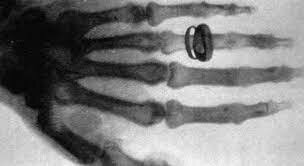

• Rayos X

Rayos X

Wilhelm Conrad Roentgen descubre los rayos X.